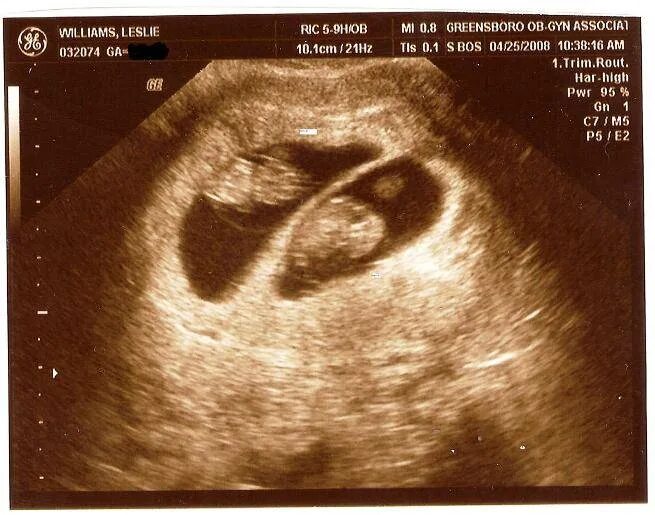

Можно ли узнать двойню